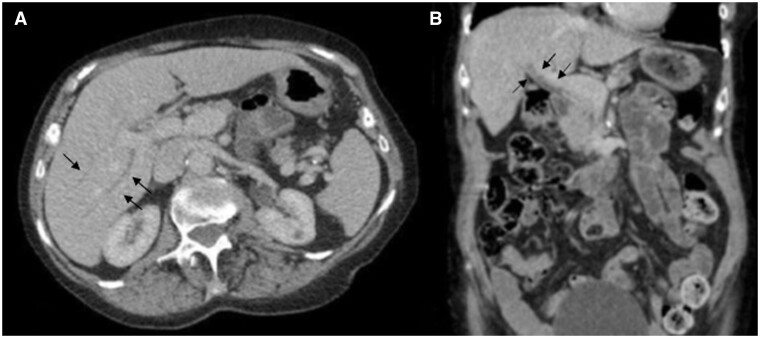

This case study describes a female patient in her late 70s who developed autoimmune cholangitis a year after finishing 35 cycles of pembrolizumab for the treatment of her non-small cell lung cancer. The diagnosis was initially missed and delayed; the patient's agoraphobia and the COVID-19 pandemic were noted as contributing factors.